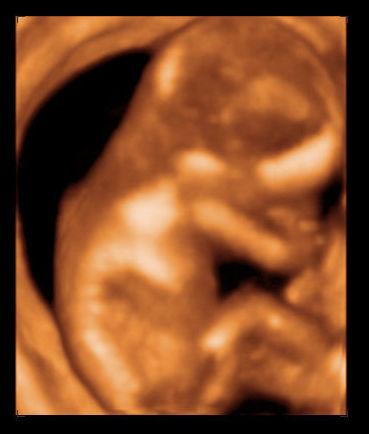

Túl vagyunk a 4D-n, Kinguska jól viselkedett, végig bent voltak apával. Pöttömke nagyon rossz passzban volt a pocakban, összegömbölyödve, hátat fordítva feküdt, mindenét takargatva, hol a szemét, hol a kis fülét fogta! :) Szinte az összes képen és a DVD 90%-án a háta látszik. :) De olyan édes volt!

És a lényeg: amit látni, azzal minden rendben, egészséges, korának megfelelően növekvő, gyönyörű KISLÁNY!!! :D :D :D

Remélem sikerül felrakni a képeket, a harmadikon picit látszik a pofija is. Tényleg csak picit. :)

Kép Kép Kép